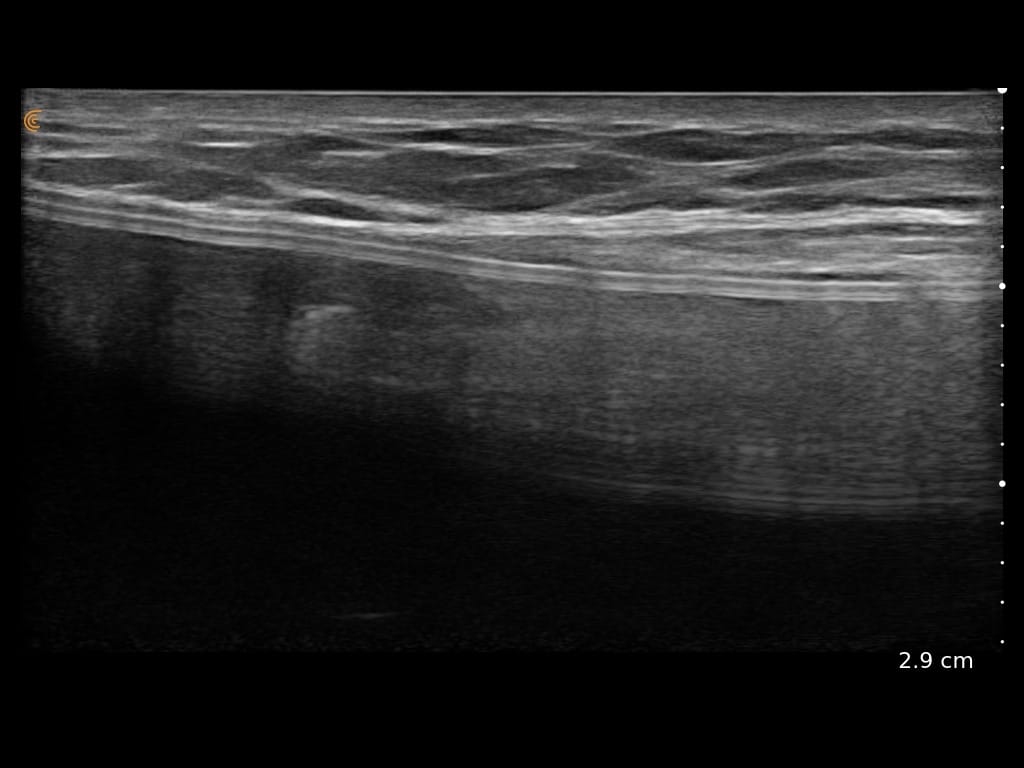

Ultrasound Imaging is very useful clinical tool to assess patient’s anatomy. In the past, ultrasound imaging was done primarily by radiologists, but is now being employed by many clinical specialties. Ultrasound use by Plastic Surgeons, however, is relatively new. Dr. Wigod has found ultrasound imaging to be a particularly valuable addition to physical exam and provides this service to his patients. Ultrasound imaging is especially useful to assess breast implants for problems such as ruptures, capsular contracture, and fluid collections. Dr. Wigod also uses ultrasound to examine other body areas and to help guide nerve blocks. Surgeon performed ultrasound does not replace radiologist performed imaging and is not for cancer screening.

For more examples of ultrasound images, go to the Breast Ultrasound Images Gallery.